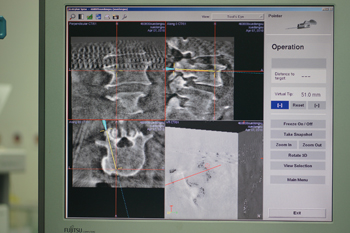

男,62岁,诊断:腰椎滑脱(L4,I度),峡部裂

术中导航